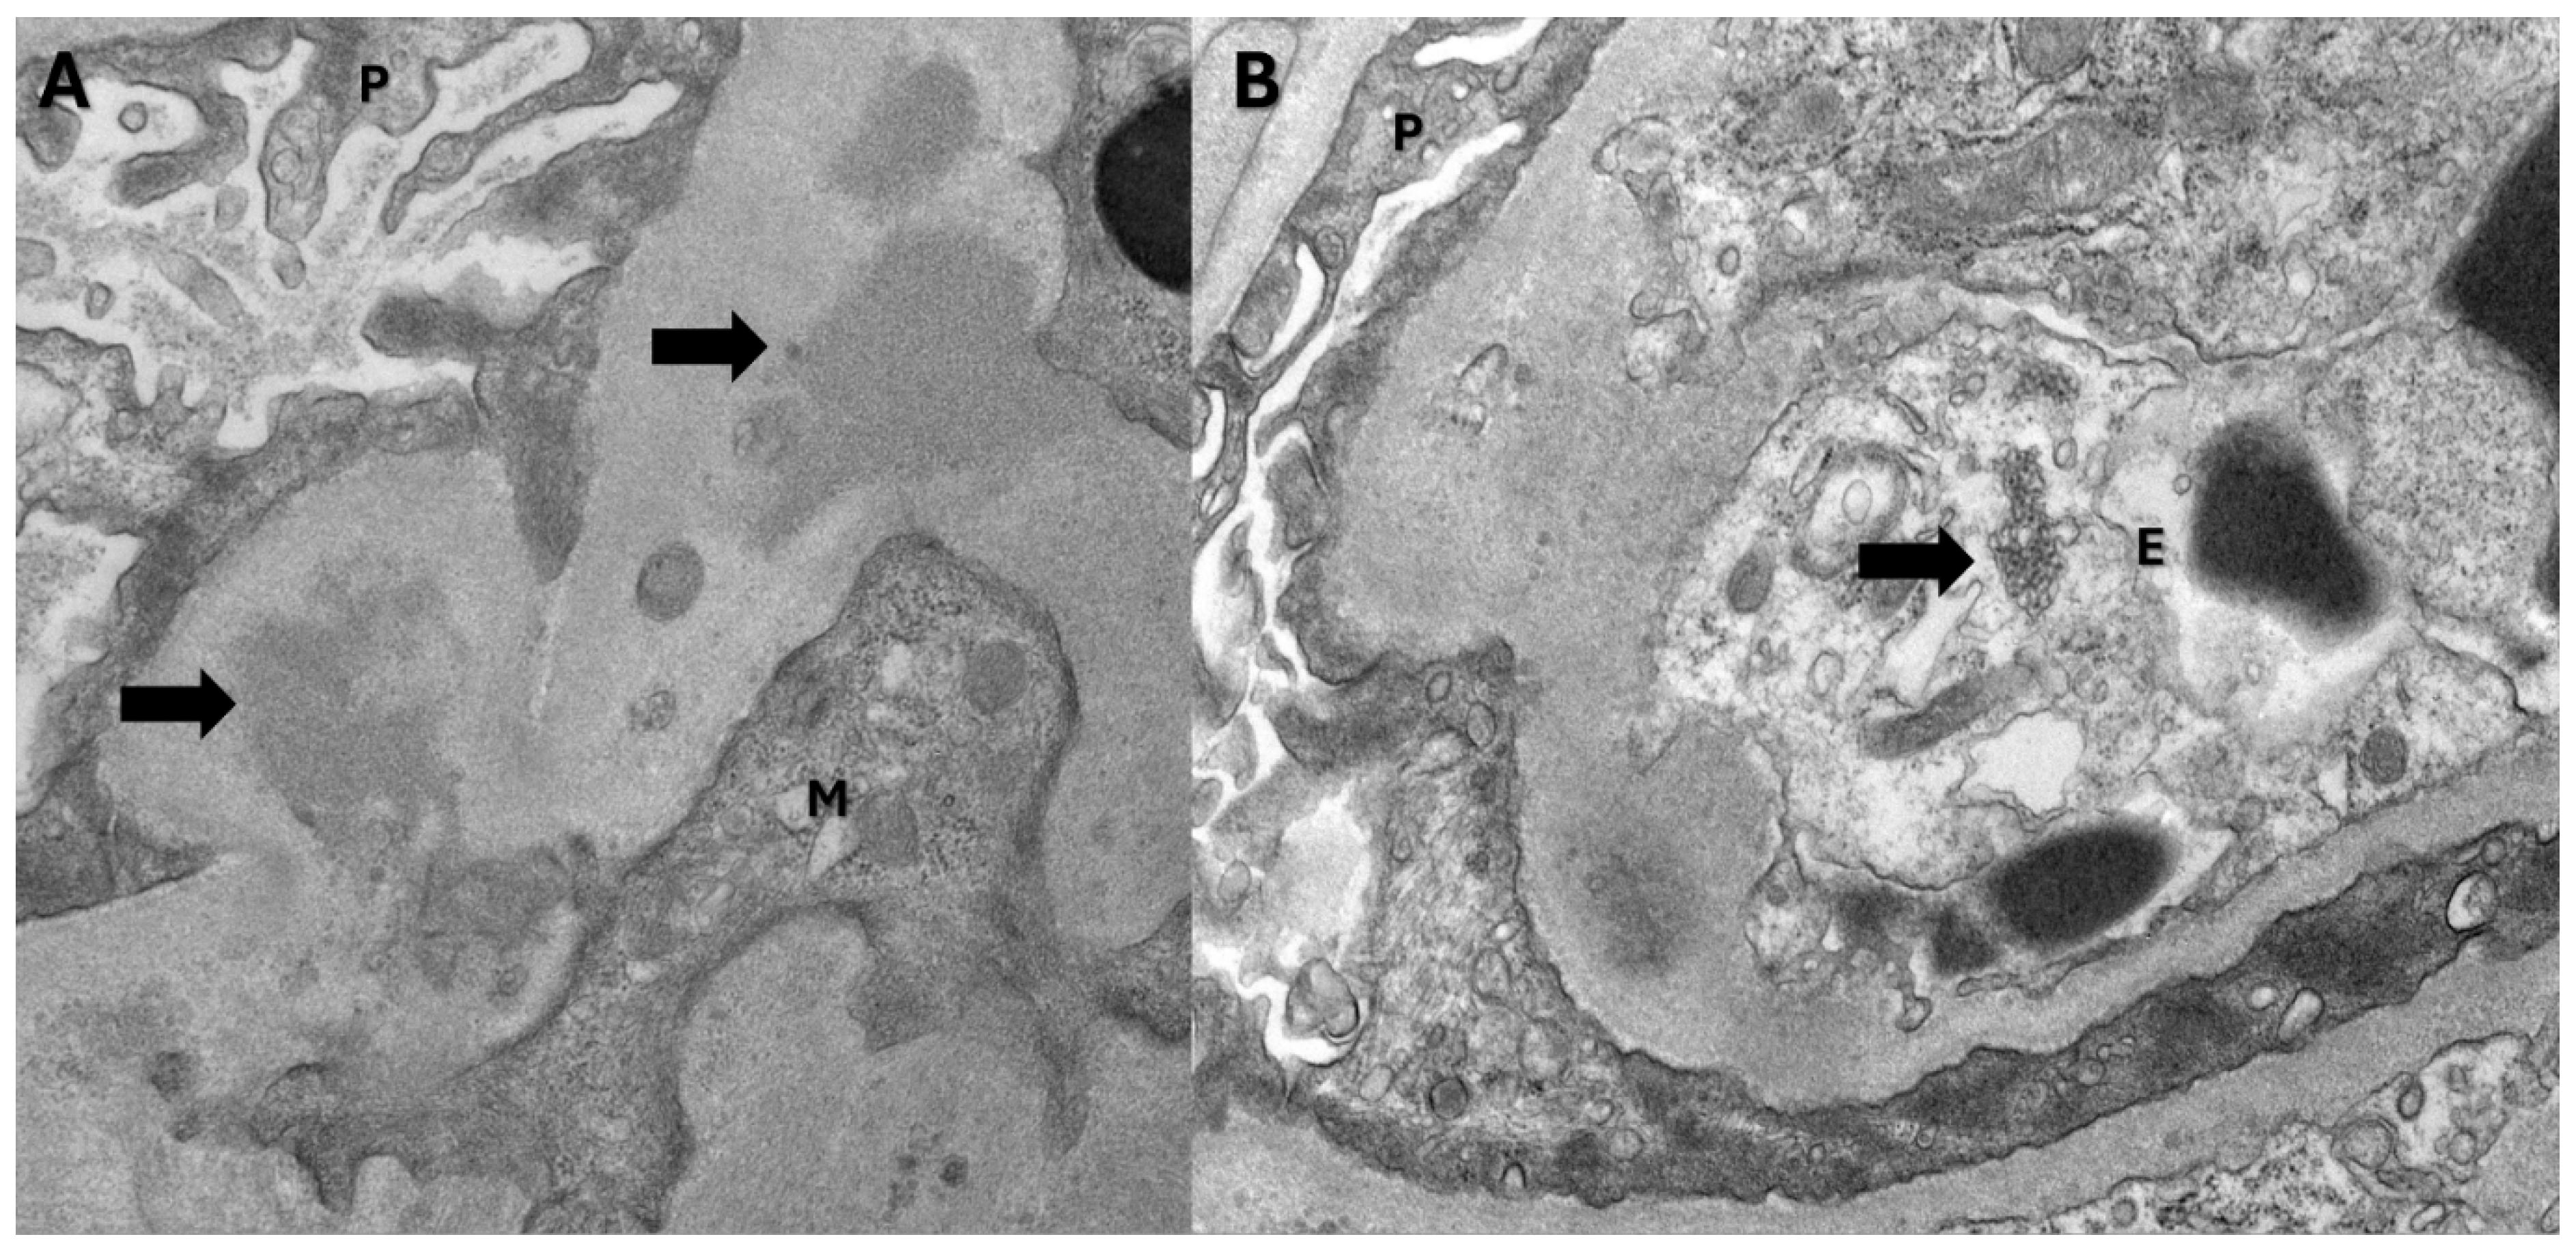

In our case, the patient had no previous history of chronic kidney disease or IgA nephropathy. His hematuria was attributed to infection-mediated crescentic glomerulonephritis secondary to COVID-19 infection. The biopsy revealed fibrinoid necrosis, crescentic glomerulonephritis, several RBC casts (in distal tubules), tubuloreticular inclusions in endothelial cells and C3 deposits supporting the diagnosis of infection-related glomerulonephritis [Figure 1and Figure 2-biopsy images] from active COVID 19 infections. We did the CD10 staining to identify the proximal tubules. Despite the absence of respiratory symptoms, the patient was treated with Remdesivir (an antiviral agent inhibiting SARS-CoV-2 RNA-dependent RNA polymerase), pulse steroids, and a prolonged prednisone taper over three months. The treatment led to the resolution of hematuria and improved renal function. This case is unique as it represents infection-related crescentic glomerulonephritis secondary to COVID-19 presenting initially with gross hematuria, a manifestation not previously described in the literature.

Figure 2. Electron microscopy findings: A. Electron dense deposits(arrows) in the mesangial region (P: Visceral epithelial cell; M: Mesangial cell). B. Tubuloreticular inclusion body(arrow) (P: Visceral epithelial cell; E: Endothelial cell).